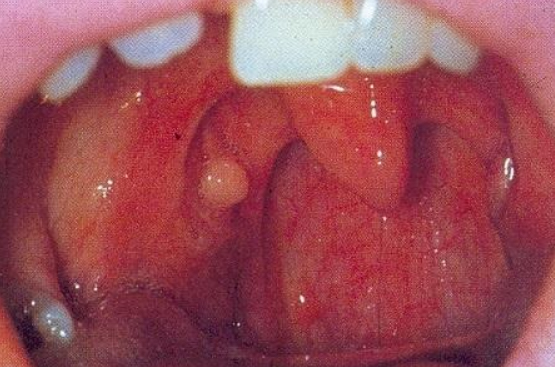

Киста в горле

Киста в данной области представляет собой округлое или мешковидное образование, заполненное жидкостью. Эти образования могут находиться в различных частях: миндалинах, языке, надгортанике, гортанном желудочке и в гортани (в подскладочном, надскладочном пространствах и на голосовых складках). Наиболее часто они встречаются в надскладочном отделе (59%), реже — в подскладочном.

Кистозные образования в гортани, как правило, являются доброкачественными. Их можно разделить на врожденные и приобретенные, которые возникают в результате гиперплазии слизистой оболочки, закупорки железистых протоков или расширения лимфатических сосудов после травмы. Появление кист на голосовых связках часто связано с постоянным раздражением этих связок. При проведении ларингоскопии такие образования выглядят округлыми и имеют гладкую серую поверхность. В некоторых случаях, когда эпителий истончается, можно увидеть содержимое кисты. Со временем стенки кисты становятся тоньше, и она начинает напоминать рыбий пузырь. Локализация в гортани может проявляться охриплостью голоса без болевых ощущений. Охриплость может усиливаться, вплоть до полной потери голоса. Также пациенты могут ощущать «инородное тело» в гортани и испытывать кашель. Наличие кистозных образований не представляет угрозы для жизни, однако они могут расти довольно активно, не проникая при этом в окружающие ткани.

Симптомы кисты в горле

Для мониторинга размеров бессимптомных кистозных образований рекомендуется проводить эндоскопическое исследование глотки и гортани. Киста на миндалине классифицируется как доброкачественная опухоль глотки и довольно часто встречается, особенно у пациентов с аденоидами и хроническим тонзиллитом. Несмотря на свою доброкачественную природу, чрезмерный рост таких образований может затруднять глотание и дыхание, а также существует риск их озлокачествления, поэтому их лучше удалять.

Пациенты с патологическими образованиями на миндалинах могут отмечать следующие симптомы:

- затруднение носового дыхания;

- ощущение «комка в горле»;

- дискомфорт (иногда боль) при глотании;

- першение в горле;

- изменение тембра голоса;

- частые простуды.

Кисты гортани небольшого размера обычно не вызывают никаких симптомов. Однако с увеличением их размера могут возникать затруднения дыхания, осиплость голоса и частые покашливания. При дальнейшем росте кистозного образования голос может полностью пропасть, а дыхание значительно усложниться. В клинической картине наблюдаются нарастающие нарушения как голосовой функции, так и дыхательной. Если киста расположена в области надгортанника, это может привести к проблемам с глотанием.

Степень выраженности симптомов зависит от стадии, локализации и размеров образования. Долгое время оставаясь бессимптомными, они могут достигать критического размера, нарушая глотание (при расположении в надгортаннике и черпалонадгортанных складках), фонацию и дыхание (при расположении в желудочках гортани и голосовых складках). При сужении дыхательной щели может развиваться острый стеноз гортани.